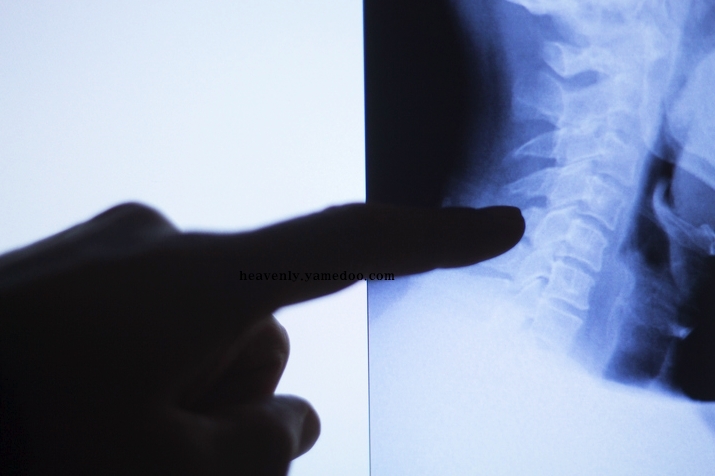

따라사 이와같은 이상증세가 발생하면 조기 검진을 받아보는 것이 무엇보다 중요하겠습니다. 본인의 건강을 위해서라도 꼭 필요하겠습니다.

하지만 목 통증이 없는데 어깨에서만 통증이 발생하거나 등 뒤쪽의 이상 증상으로 인해서 다른 질환으로 착각할 수 있기때문에 자기자신이 직접 목디스트 자가진단을 해 보는 것이 좋습니다. 그래서 목디스크 자가진단법을 준비해 봤습니다.